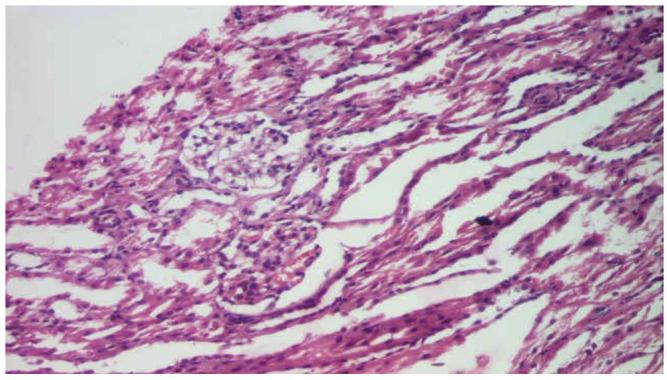

A 36% case of nephrotic syndrome was corticoresistant, with the mean age at onset of patients with SRNS being 9.18 years, compared to KDIGO studies in which the corticosteroid resistance is 10-20%. Renal biopsy was performed in 80.88% children with SRNS and was allowed the evaluation of the activity and chronicity index. Total remission was obtained in 44.01% children with SRNS. The correlation of the anatomopathological aspects with the evolution is not statistically significant (p = 0.76), observing different therapeutic responses to all the analyzed histological types.

36%的肾病综合征病例为皮质类固醇抵抗型,SRNS患者的平均发病年龄为9.18岁,而KDIGO研究中的皮质类固醇抵抗率为10 - 20%。80.88%的SRNS患儿进行了肾活检,从而能够评估活动度和慢性指数。44.01%的SRNS患儿实现了完全缓解。解剖病理学特征与病情发展的相关性无统计学意义(p = 0.76),对所有分析的组织学类型观察到不同的治疗反应。